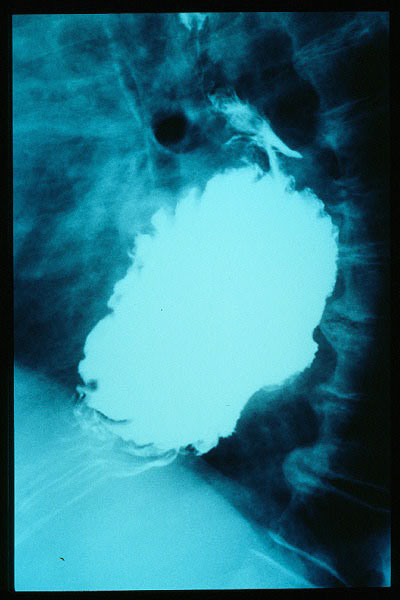

Hernia de hiato gigante.